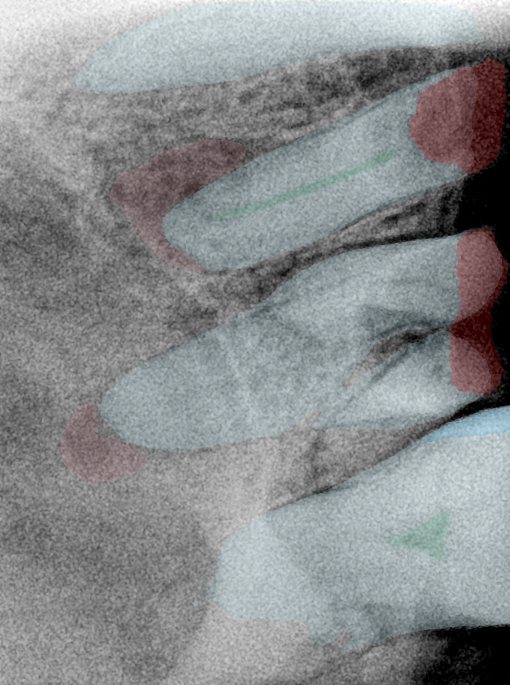

CR/DR 牙齿分割阶段记录

当前进展

- 完成了 CR/DR 牙齿相关分割训练

- 当前结果已经达到阶段预期,但仍有细节问题需要继续处理

相关测试

遇到的问题

- 训练过程中出现过 mask 下移问题

- 部分结果会出现 box 填充异常

- mask 边缘仍然有比较明显的锯齿感